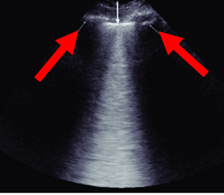

This anatomical structure is shown by the red arrows in this "bat wing" representation of the anterior lung field.

What are... the ribs?